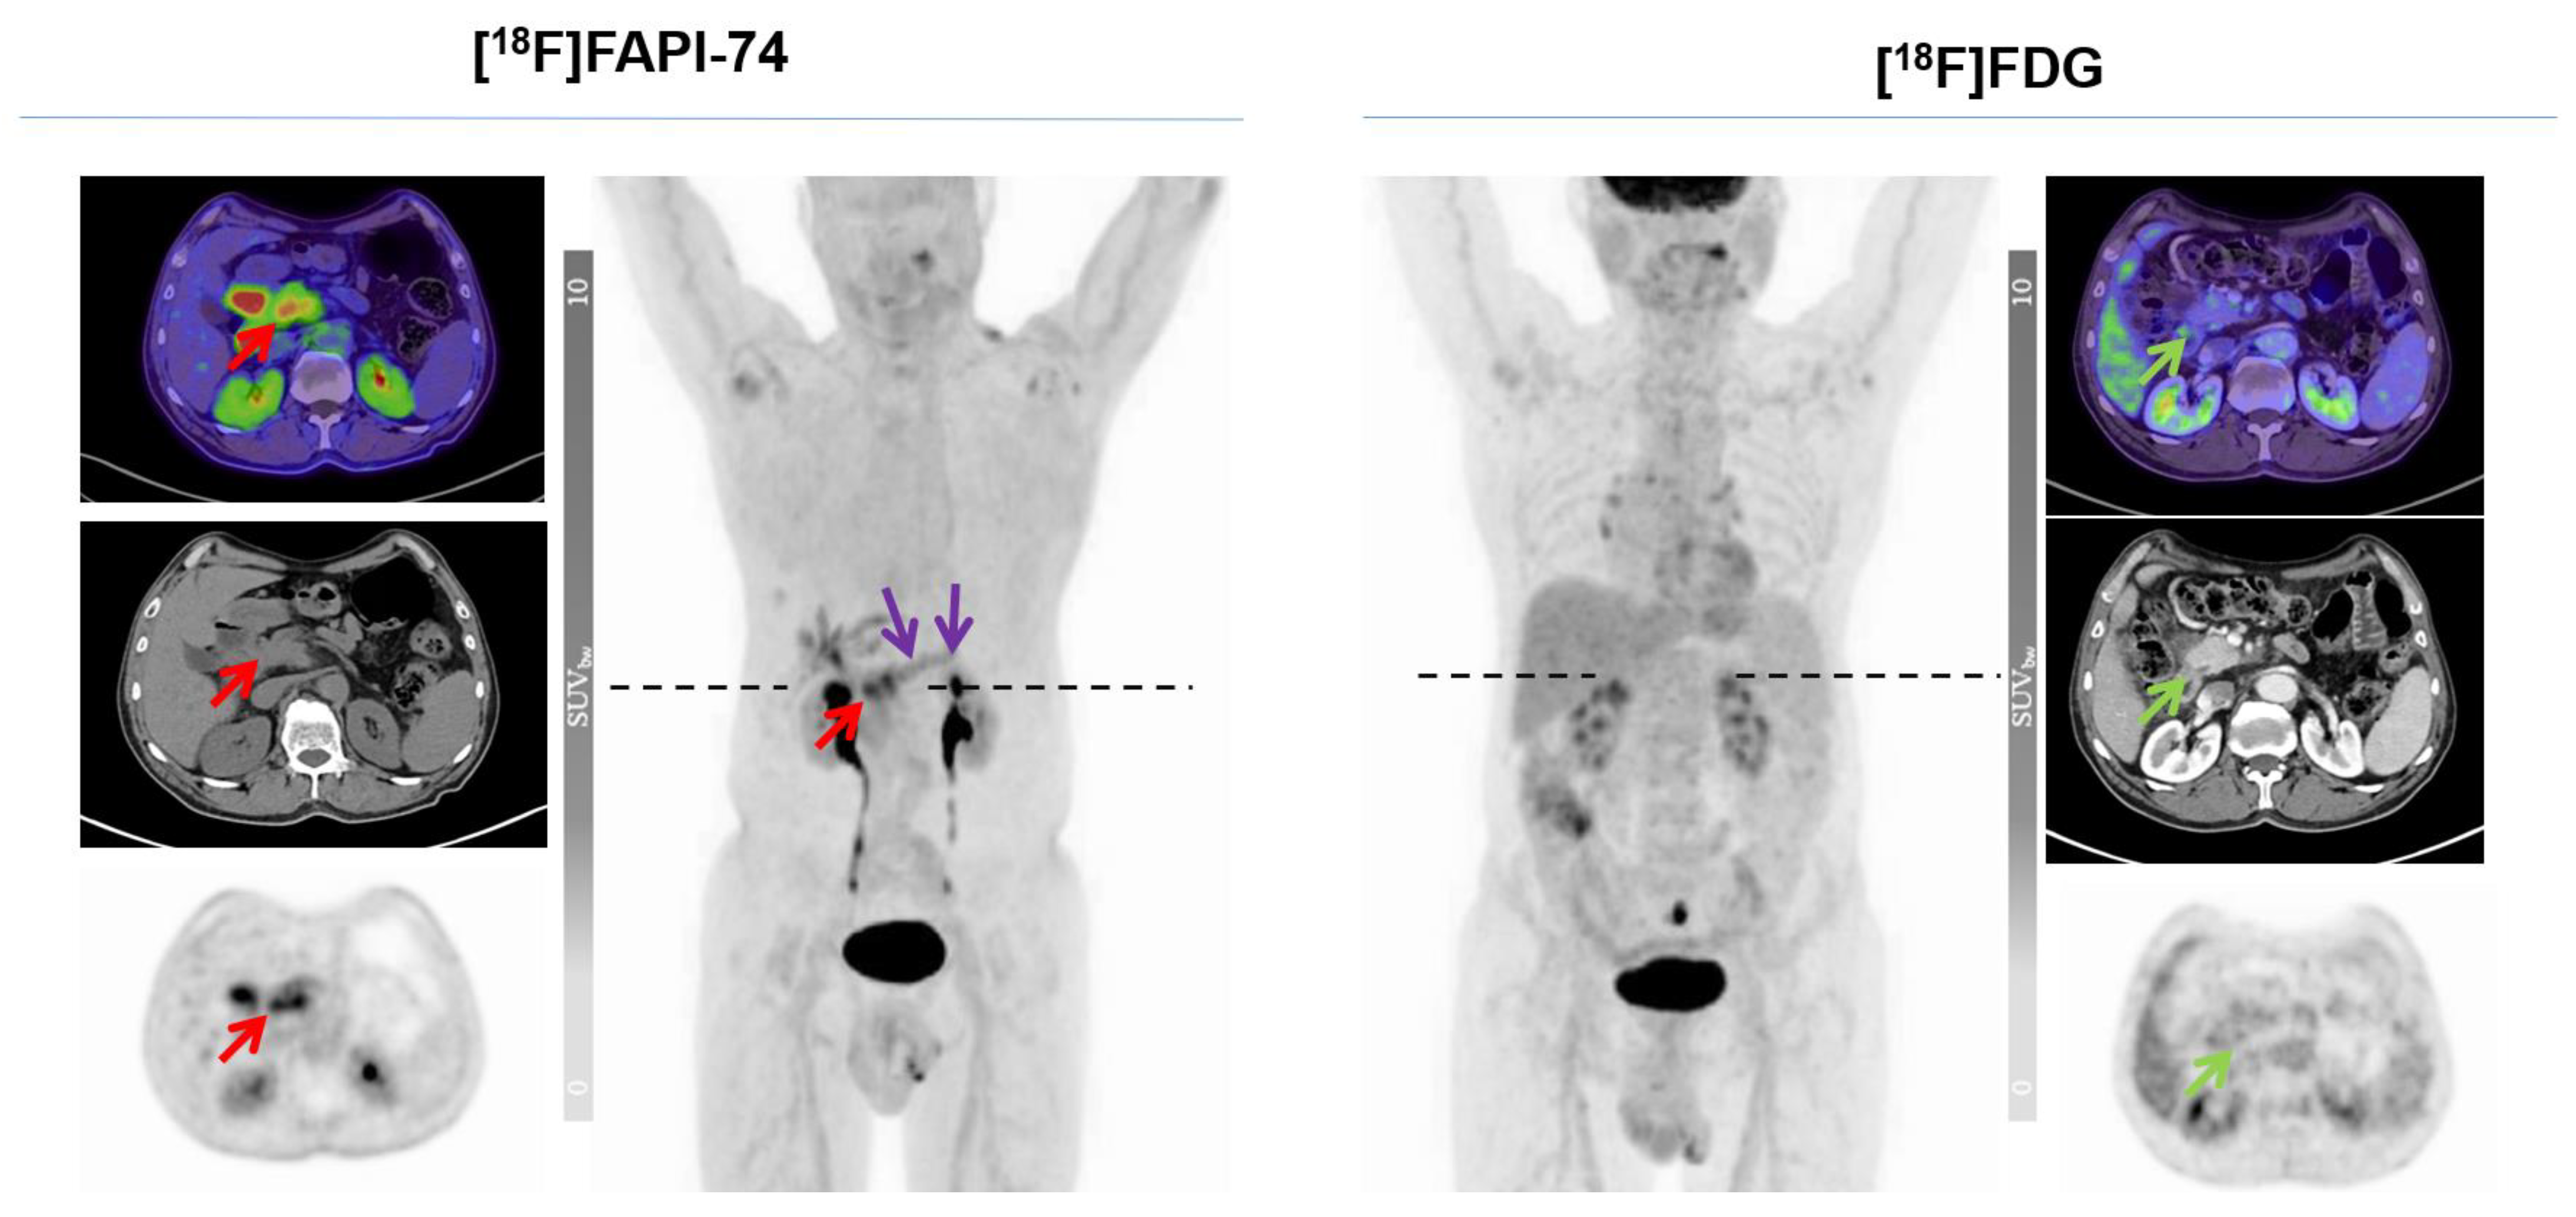

3.3. [18F]FAPI-74 Uptake in Tumor Lesions

3.4. [18F]FAPI-74 in PDAC with Confounding Pancreatitis